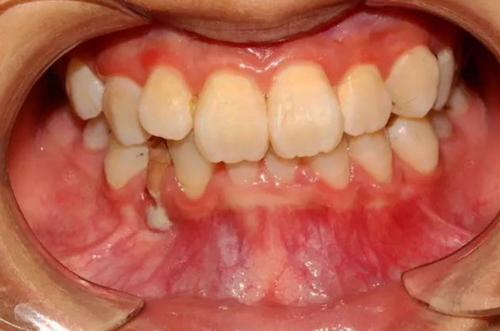

本案:患兒,女,14歲,因牙齒矯正來院,檢查見83滯留,43未見萌出,拍片發(fā)現(xiàn):43埋伏阻生于31、41、42根尖下方,按照正畸診療計劃,擬行43拔除術(shù)。

口腔牙列照片